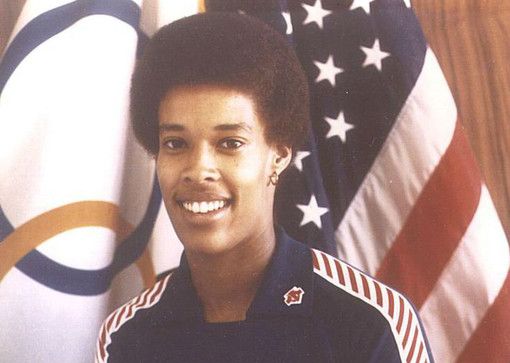

Boleznennyj dar nikkolo paganini redkij sindrom marfana priznaki sposoby lecheniya i nasledovanie u detej sindrom marfana kto bolel iz znamenitostej (Тип файлу jpg)

Boleznennyj Dar Nikkolo Paganini Redkij Sindrom Marfana Priznaki Sposoby Lecheniya I Nasledovanie U Detej Sindrom Marfana Kto Bolel Iz Znamenitostej

Chelovek i ego zdorove sindrom marfana sekrety andersena paganini i chukovskogo obsuzhdenie na liveinternet rossijskij servis onlajn dnevnikov (Тип файлу jpg)

Chelovek I Ego Zdorove Sindrom Marfana Sekrety Andersena Paganini I Chukovskogo Obsuzhdenie Na Liveinternet Rossijskij Servis Onlajn Dnevnikov